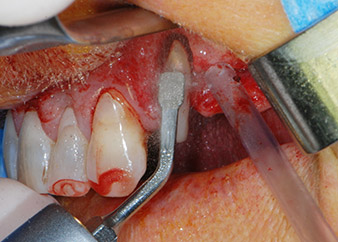

kompletter Verlust von Knochen und Attachment

Abb. 2 und 3: Bei der Freilegung einen Monat nach endodontischer Revision und Beginn einer systematischen Parodontalbehandlung weist die bukkale Wurzel des Zahns 24 einen kompletten Verlust von Knochen und Attachment auf.

Einen Monat nach dem Eingriff waren sowohl die Schmerzen als auch die Entzündung an Zahn 24 minimal, die Zahnbeweglichkeit lag jedoch noch bei Miller-Klasse 2. Nach Freilegung und Reinigen des infizierten periapikalen und periradikulären Gewebes wurde das Ausmaß des Knochendefizits deutlich (Abb. 2 und 3).

An der bukkalen Wurzel fehlte der gesamte vestibuläre und distale Knochen. Das Attachment beschränkte sich weitgehend auf die palatinale Wurzel, was die anfängliche schlechte Prognose unterstreicht. Auch Zahn 27 wies ein verringertes horizontales Attachment (vgl. Abb. 12) und eine kleine apikale Aufhellung (Abb. 1) auf, allerdings ohne klinische Symptome.